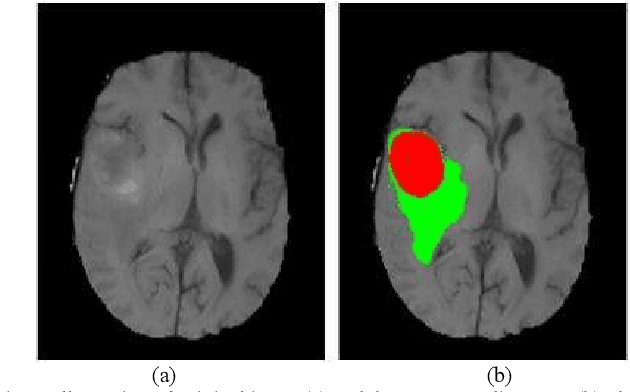

Abstract:Glioma grading before the surgery is very critical for the prognosis prediction and treatment plan making. In this paper, we present a novel scattering wavelet-based radiomics method to predict noninvasively and accurately the glioma grades. The multimodal magnetic resonance images of 285 patients were used, with the intratumoral and peritumoral regions well labeled. The wavelet scattering-based features and traditional radiomics features were firstly extracted from both intratumoral and peritumoral regions respectively. The support vector machine (SVM), logistic regression (LR) and random forest (RF) were then trained with 5-fold cross validation to predict the glioma grades. The prediction obtained with different features was finally evaluated in terms of quantitative metrics. The area under the receiver operating characteristic curve (AUC) of glioma grade prediction based on scattering wavelet features was up to 0.99 when considering both intratumoral and peritumoral features in multimodal images, which increases by about 17% compared to traditional radiomics. Such results shown that the local invariant features extracted from the scattering wavelet transform allows improving the prediction accuracy for glioma grading. In addition, the features extracted from peritumoral regions further increases the accuracy of glioma grading.